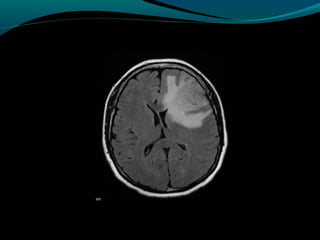

Glioblastoma

RM:

Sinal heterogêneo em T1, T2 e FLAIR; (necrose, cistos,

hemorragia, neovascularização); mas predomina

hipointensidade em T1 e hiper em T2 e FLAIR;

Realce difuso e heterogêneo pelo Gd;

Redução do NAA

Aumento do Co

Redução da razão Mi/Cr

Picos de lipídeos e lactato

Centro necrótico não restringe à difusão;

Na perfusão: aumento do CRBv máximo;

OBS: capacidade invasiva impede ressecabilidade total;